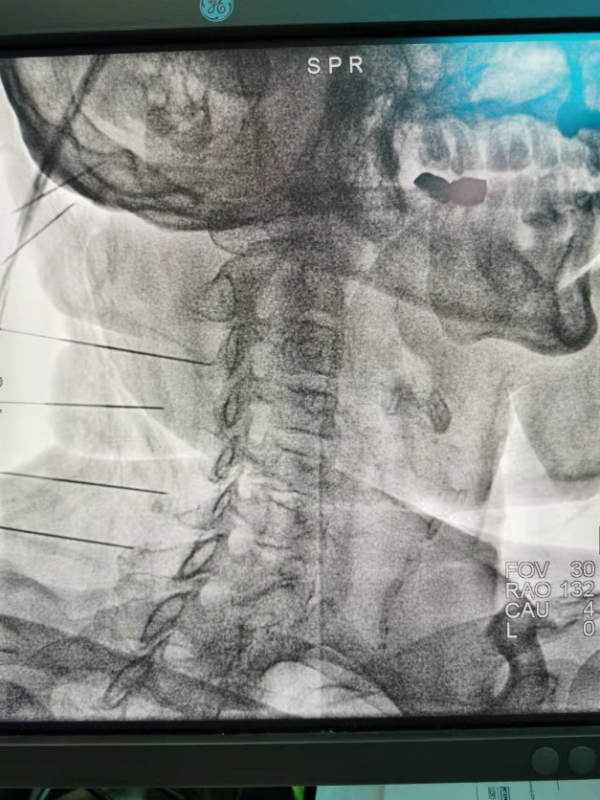

在明確了病因以後,李娟紅疼痛團隊為劉先生做了“頸椎神經超微創脈衝射頻治療”,按照劉先生自己的說法:就是在脖子上紮了幾針,頭痛就好多了,當天就能踏踏實實睡著覺了,很多年都沒這麼舒服地睡覺了。